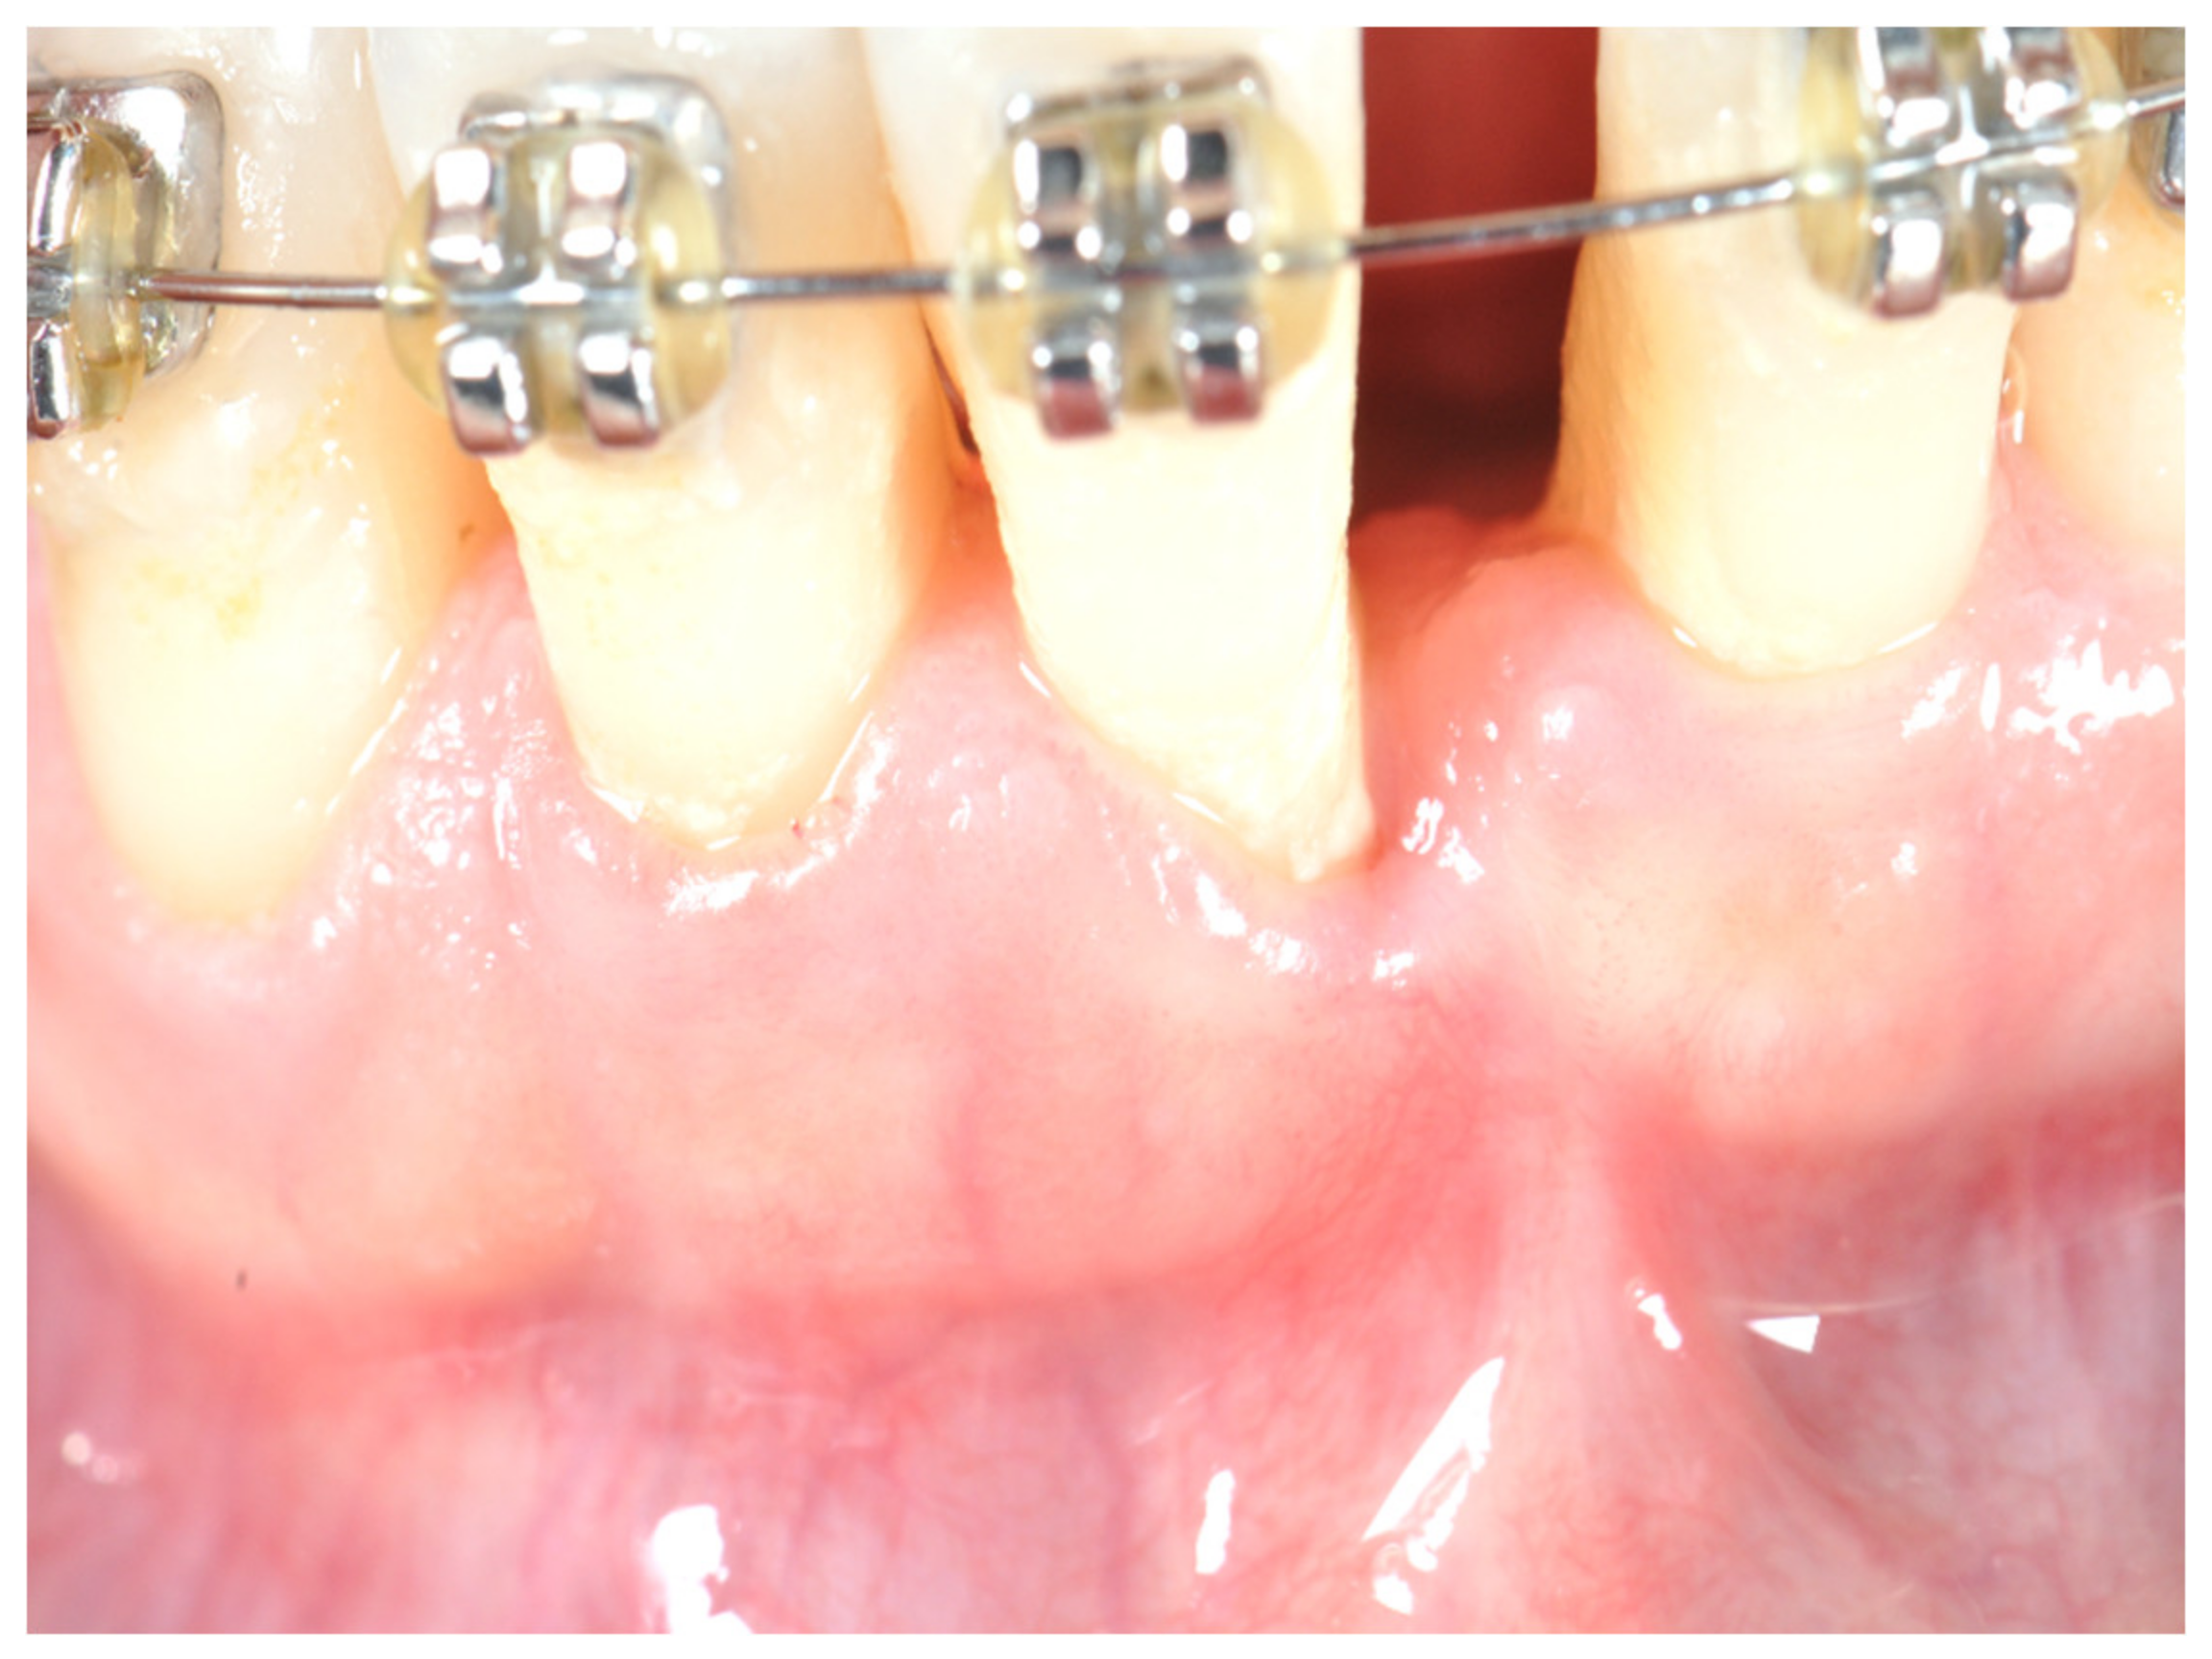

2. Materials and Methods

- Using a #15 blade, an intrasulcular incision was made and a partial thickness flap was raised. The recipient site was prepared by sharp dissection to create a bleeding periosteal bed free of all muscle attachments;